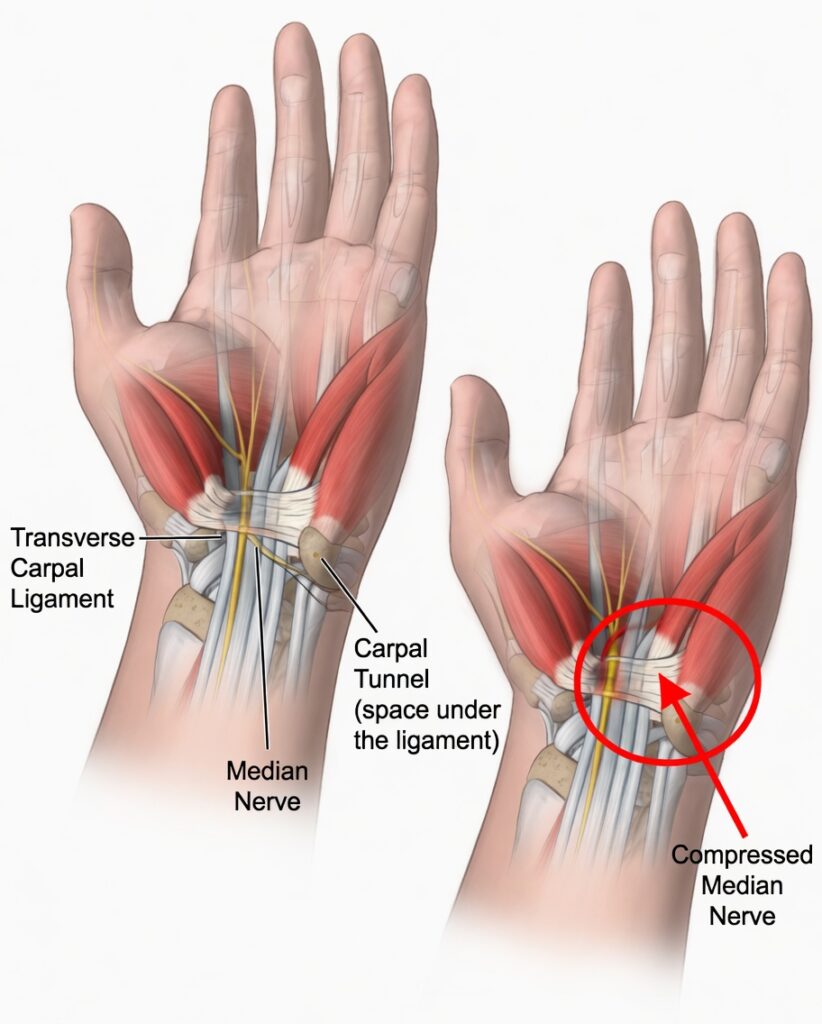

What Is Carpal Tunnel Syndrome?

The carpal tunnel is a narrow passageway in the wrist through which the median nerve runs. When this nerve is compressed due to swelling, inflammation, or constant pressure, it can lead to discomfort, numbness, weakness, and pain in the hand and wrist.